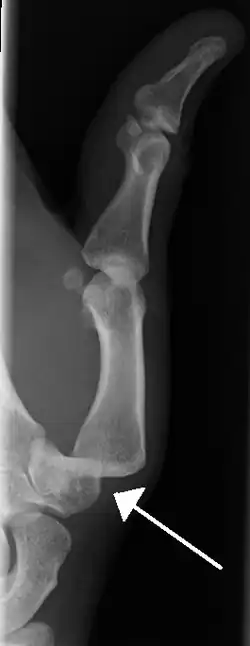

-

Dislocation of the left index finger -

Dislocation of the carpo-metacarpal joint.

Radiograph of right fifth phalanx dislocation resulting from bicycle accident -

Right fifth phalanx dislocation resulting from bicycle accident